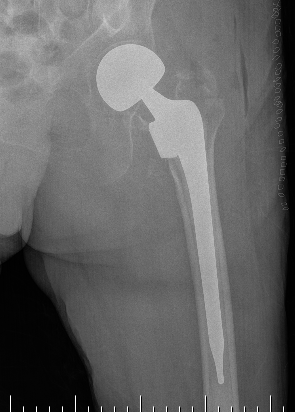

Hemiarthroplasty / Total hip replacement

Indications

- severe comminution

- salvage of failure of previous fixation

Technical

- may need calcar replacement

- may need greater trochanter fixation